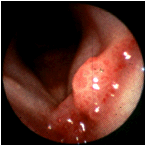

A patient with asthma and symptoms of gastroesophageal reflux. The whole supraglottic larynx is bright red, consistent with an acid burn. Although red, the epiglottis does not appear to be thickened. Reflux can cause inflammation of almost any part of the upper aerodigestive tract, including the nose. (Selner slide #48) |

![]() |